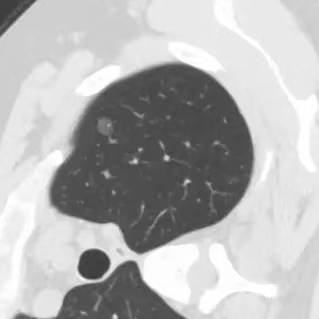

健康直通车: 健康是生命的宝贵财富,也是幸福生活的基石。为了更好地服务广大百姓,传播健康知识,葫芦岛市第二人民医院推出“健康直通车”专题栏目,将专业的医学知识以通俗易懂的方式传递给每一位市民,掌握科学的疾病预防方法,共同构筑健康中国的坚实基石。 什么是肺结节 肺结节是指肺内直径小于或等于3cm的类圆形或不规则形病灶,影像学表现为密度增高的阴影。大于3cm的称肿块。肺结节依其密度不同可分为实性结节、部分实性结节、磨玻璃结节,其中部分实性结节的恶性可能性最大,磨玻璃结节次之,实性结节尤其是小的实性结节结节最可能是良性的。 肺结节的常见病因 1、良性(约90%) 🔸 感染:结核、真菌、细菌性肺炎后遗留的瘢痕; 🔸 非感染:错构瘤(良性肿瘤)、炎性假瘤、血管瘤等。 2、恶性(约10%) 🔸原发性肺癌(如腺癌、鳞癌); 🔸转移性肿瘤(其他器官癌症转移至肺)。 如何根据影像判断肺结节性质 1、依据结节大小判断 🔸小于0.5cm的肺结节绝大多数都是良性的,属于微小结节。即使部分小于0.5cm肺结节是恶性的,但是适当的观察不影响预后。每年复查一次胸部CT就可以。 🔸大于0.5cm持续存在的纯磨玻璃结节,观察6个月,若持续存在,不管有无进展均多数是恶性的,视患者意愿,手术可以立即做也可观察至进展再做,不影响预后。 🔸大于0.8cm的部分实性结节恶性可能性非常大,应积极评估结节边缘毛刺、分叶、胸膜凹陷等征象。 🔸若实性部分大于0.5cm,恶性率显著提高。若在3~6个月随访期间实性部分增大或者总体部分增大,都可以考虑手术切除。而即使小于0.8cm的部分实性结节也需3个月就复查对比。 2、依据肺结节形态 如CT上提示病灶形态不规则、毛刺、分叶、胸膜凹陷、空泡征、血管集束征等,符合恶性肿瘤的征象。 🔸结节与正常肺组织之间界限非常清楚的恶性可能性大。 🔸结节密度不均呈混杂密度或均匀较大纯磨玻璃结节也基本是恶性的。 🔸有胸膜牵拉(不管是肺表面的脏层胸膜还是叶间裂部位的胸膜)的恶性可能性大。 🔸结节有浅分叶、细毛刺,密度较高而与周围肺组织边界不清的恶性可能性大。 🔸磨玻璃或混合磨玻璃结节存在小空洞的恶性可能性大。 🔸影像上似慢性炎表现,而没有炎症相关的其他异常,特别当所谓炎症区域内部或一侧与正常肺组织之间界限非常清楚的基本上是恶性的。 3、从结节发展情况来看 所有随访中增大进展的都需要考虑恶性可能,不进展而持续存在的纯磨玻璃结节也需考虑恶性。 葫芦岛市第二人民医院肺结节诊治中心孙振教授深耕肺结节领域四十余载,凭借对临床实践的执着钻研与深厚积淀,在肺结节精准诊断及鉴别诊断领域形成独到见解。他系统总结海量临床病例,创新性提炼出一套科学化、规范化的肺结节全周期诊疗体系,尤其在早期微小结节的影像特征识别、良恶性风险分层等方面积累了丰富经验,为众多患者提供了精准、高效的诊疗方案。 人民医院·人民名医 孙振 主任医师 三级教授 ·葫芦岛市第二人民医院胸外科主任、肺结节诊治中心主任 ·中国医科大学客座教授 ·原央企总医院著名胸外科专家 ·辽宁省医学会胸外科委员 ·辽宁省抗癌协会肺癌专业委员会委员 ·辽宁省细胞生物学学会食管癌专业委员会理事 ·主持多项科研成果获科技成果奖、科技进步奖、国家专科奖项 医学成就 从事胸外科临床工作近40年,担任胸外科首席专家及科室主任20余年,是我省胸外科领军人物,推动肺癌、食管癌等胸部肿瘤外科的规范化诊疗,在央企总医院牵头成立了肺结节诊疗中心,率先开展CT引导下肺内小结节定位切除,既确切完整切除肺内小结节,又降低肺功能损害。 专业特色 擅长肺癌、食管癌的外科手术和综合治疗,在各类高难度胸外伤手术治疗、胸腔镜微创手术、胸腺瘤手术及复杂并发症处理方面具有高深造诣,尤其擅长肺癌早期诊断,胸部小结节CT早期肺癌的鉴别等。完成各类高难度胸外科手术5000余例,其中微创手术占比达90%,治愈率达98%,多项业务填补省内空白。 开展的高难手术 胸腔镜肺部结节微创手术、肺癌根治术、食管癌根治术、各种纵隔肿瘤切除术、胸骨后甲状腺手术及胸部复合性外伤的抢救手术等。